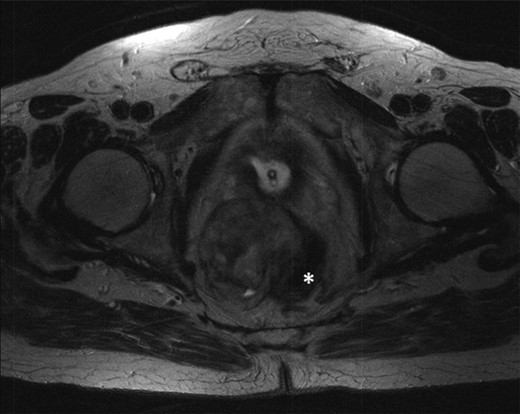

T2-weighted axial showing the same mass lying adjacent to the anterior wall of the rectum (*).

T2-weighted axial images after 3 months of imatinib mesylate therapy. The mass has shown a significant reduction in size (white star).